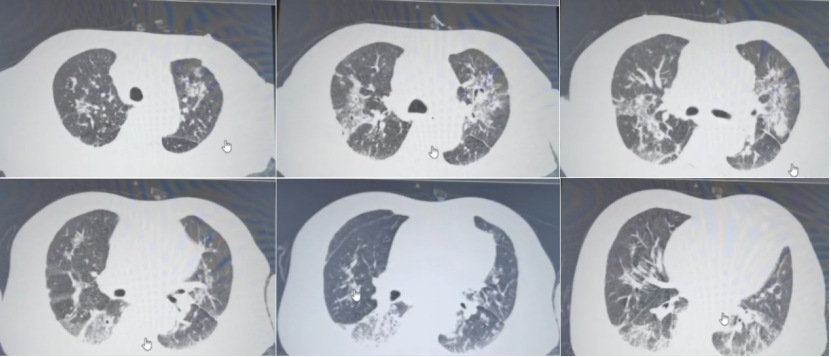

• 入院后胸部增强CT(2022-08-10)肺部结节样病变和空洞样病变较前明显进展(图2)

图片

2  患者胸部增强CT(2022-08-10)